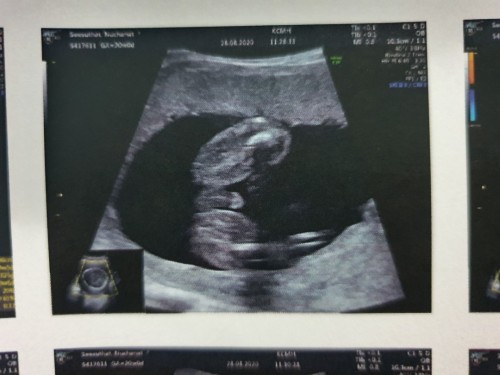

อันนี้คือภาพอัลตร้าซาวเพศชายใช่ไหมคะ?

ตรงนี้มันคือจู๋ ใช่ไหมคะ? คือได้มาหลายภาพ แต่ไม่รุ้ว่าภาพที่บอกเพศใช่ภาพนี้หรือป่าว หมอบอกน้องเพศชาย แต่จะหาภาพส่งไปให้คุณปู่-ย่าดูอยุ่ค่ะ

ใช่ค่ะ นี่ของเรา ตอนลูกชายคนแรก ชัดเจนมากๆๆๆ

ไม่น่าจะใช่นะคะ ของเราพวงนิดเดียว😅😅